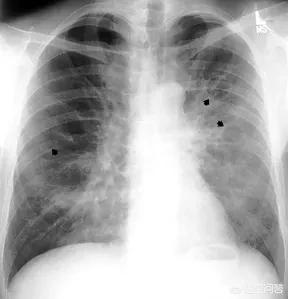

或者,至少在一年以前,曾经有过和艾滋病感染者的高危性行为,虽然没有急性期症状,但1~10年以后,出现免疫力逐渐下降引起的各种机会感染,比如带状疱疹、不明原因的肺炎、结核、长期腹泻、体重减轻等问题的,也要考虑是否感染了艾滋病。

艾滋病不是通过症状来诊断的,除非是免疫力遭受极大的破坏,出现上面所说的以孢子菌肺炎为主的机会感染,或者出现卡波西肉瘤等平常人不易得的一些病,才需要考虑是不是已经艾滋病发病了。